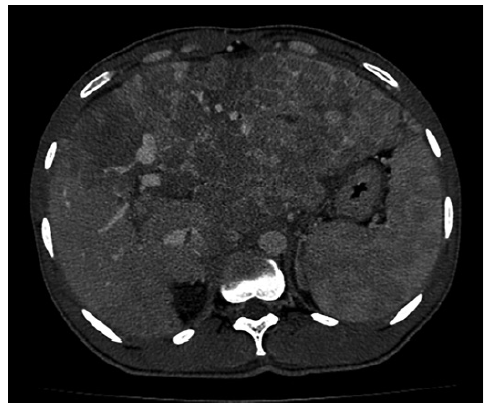

A 25-year-old male patient from Guinea, in Portugal for 6 months, with no known medical history presented with a 2-week history of fatigue, exertional dyspnea, anorexia, and weight loss. He also mentioned abdominal pain for the last 4 days. The patient consumed 20 g of alcohol per week and had no history of drug consumption or tobacco smoking habits. He was employed as a construction worker and did not have any relevant travel history. Physical examination showed a systolic murmur in the tricuspid area, an enlarged liver and right upper quadrant pain, with no ascites or signs of chronic liver disease stigmata. The electrocardiogram revealed sinus tachycardia with a right bundle branch block and the chest radiograph showed an enlarged cardiac silhouette. An echocardiogram showed an intracardial mass in the right atrium (RA) (80 mm × 64 mm), obstructing the tricuspid valve and causing functional stenosis. His laboratory tests showed normocytic anemia (hemoglobin 11.6 g/dL [ref. 13-17.5]), slightly elevated liver enzymes (AST 91 U/L [ref. 0-34], ALT 68 U/L [ref. 10-49], GGT 68 U/L [ref. 0-60], ALP 393 U/L [ref. 35-105]), with normal bilirubin (1.12 mg/dL [ref. <1.2]), and elevated NT-proBNP (457 pg/mL [ref. <300]). He underwent a computed tomography scan of the thorax, abdomen, and pelvis, which revealed multiple coalescent lesions evolving mainly the left and caudate lobes, consistent with multicentric HCC (shown in Fig. 1). Additionally, macrovascular invasion was observed in the left portal vein, middle suprahepatic veins, and inferior vena cava, extending into the lumen of the right ventricle and atrium. The intracardiac component measured 9 × 7.5 × 6 mm (AP ×T×L)(shown in Fig. 2). The computed tomography scan also identified bilateral pulmonary secondary lesions and signs of multiple segmental and sub-segmental bilateral pulmonary embolisms. Fur-ther investigation revealed an HBV infection (AgHbs positive, anti-Hbs negative, AgHbe positive, anti-Hbe negative) with a viral load of 1,160,000 IU/mL and an alpha-fetoprotein of 357,440 ng/mL (ref. <7). The patient was classified as Barcelona Clinic Liver Cancer (BCLC) Stage C due to the presence of extra-hepatic spread and portal invasion.

Fig. 2. CT scan of the thorax. a Macro-vascular invasion of the left portal vein, middle suprahepatic veins, and inferior vena cava. b Tumoral extension into the lumen of the right ventricle and atrium, with an intracardiac component measuring 9 × 7.5 × 6 mm (AP × T × L). CT, computed tomography.